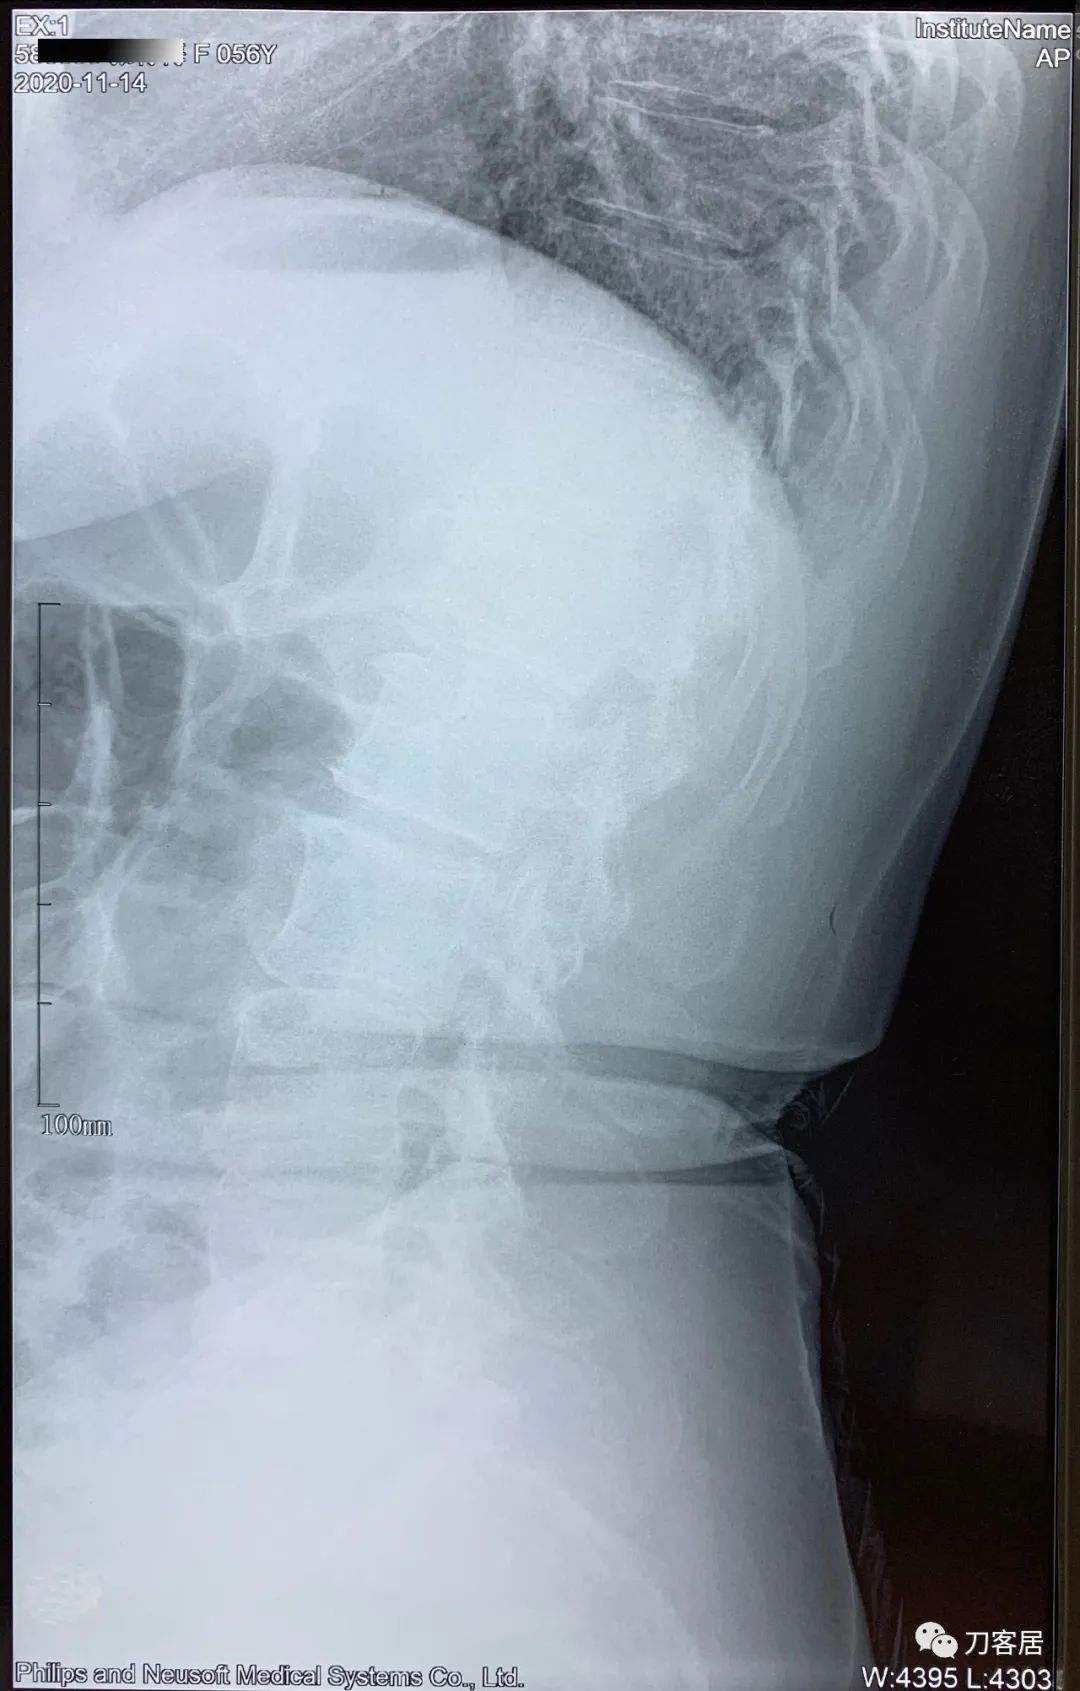

患者自2020年8月4日始头晕,2020年8月25日双手麻,双胳膊麻,于兰大二院定西分院检查颈椎MRI及腰椎X线片, 提示1. 颈椎生理曲度变直,2. 颈椎骨质增生,3. 颈椎间盘变性,颈4-7椎间盘轻度膨隆,4. 腰椎侧弯畸形。

2021年5月17日,西京医院骨科门诊找我就诊,自带影像学检查资料提示腰椎侧弯,腰3-4,腰4-5椎间盘突出,黄韧带肥厚,椎管狭窄。

建议其查双光子骨密度,骨盆正位片以及腰椎间盘平扫。腰椎正侧位X线片以及动力位片,站立位脊柱全长正侧位X线片,以了解其是否有骨质疏松,并了解脊柱侧弯情况,腰椎局部X线表现情况和腰椎间盘突出和椎管狭窄情况。

从这个患者的影像资料分析,颈椎间盘突出问题不大,没有明确的上位神经元损伤表现,所以,不考虑颈椎和胸椎问题。腰椎侧弯畸形,但不严重。因为存在腰椎侧弯,使得腰椎MRI在扫描切面的时候,显示的椎间盘突出或椎管狭窄会有一定的误差,所以,又加做了经椎间盘的CT平扫,影像表现并不严重,综上,腰椎间盘突出,腰椎管狭窄,腰椎侧弯,不考虑手术治疗。同时,患者的主要痛苦是心理疾病,而不是器质性疾病,所以,以心身疾病治疗为主。虽然患者骨密度检查结果提示正常,但X线片显示骨质疏松,且其症状也与骨质疏松的症状有符合之处,比如静息痛,不能入睡,动作及姿势变换时痛加重等,所以,给予实验性抗骨质疏松治疗,以观疗效。